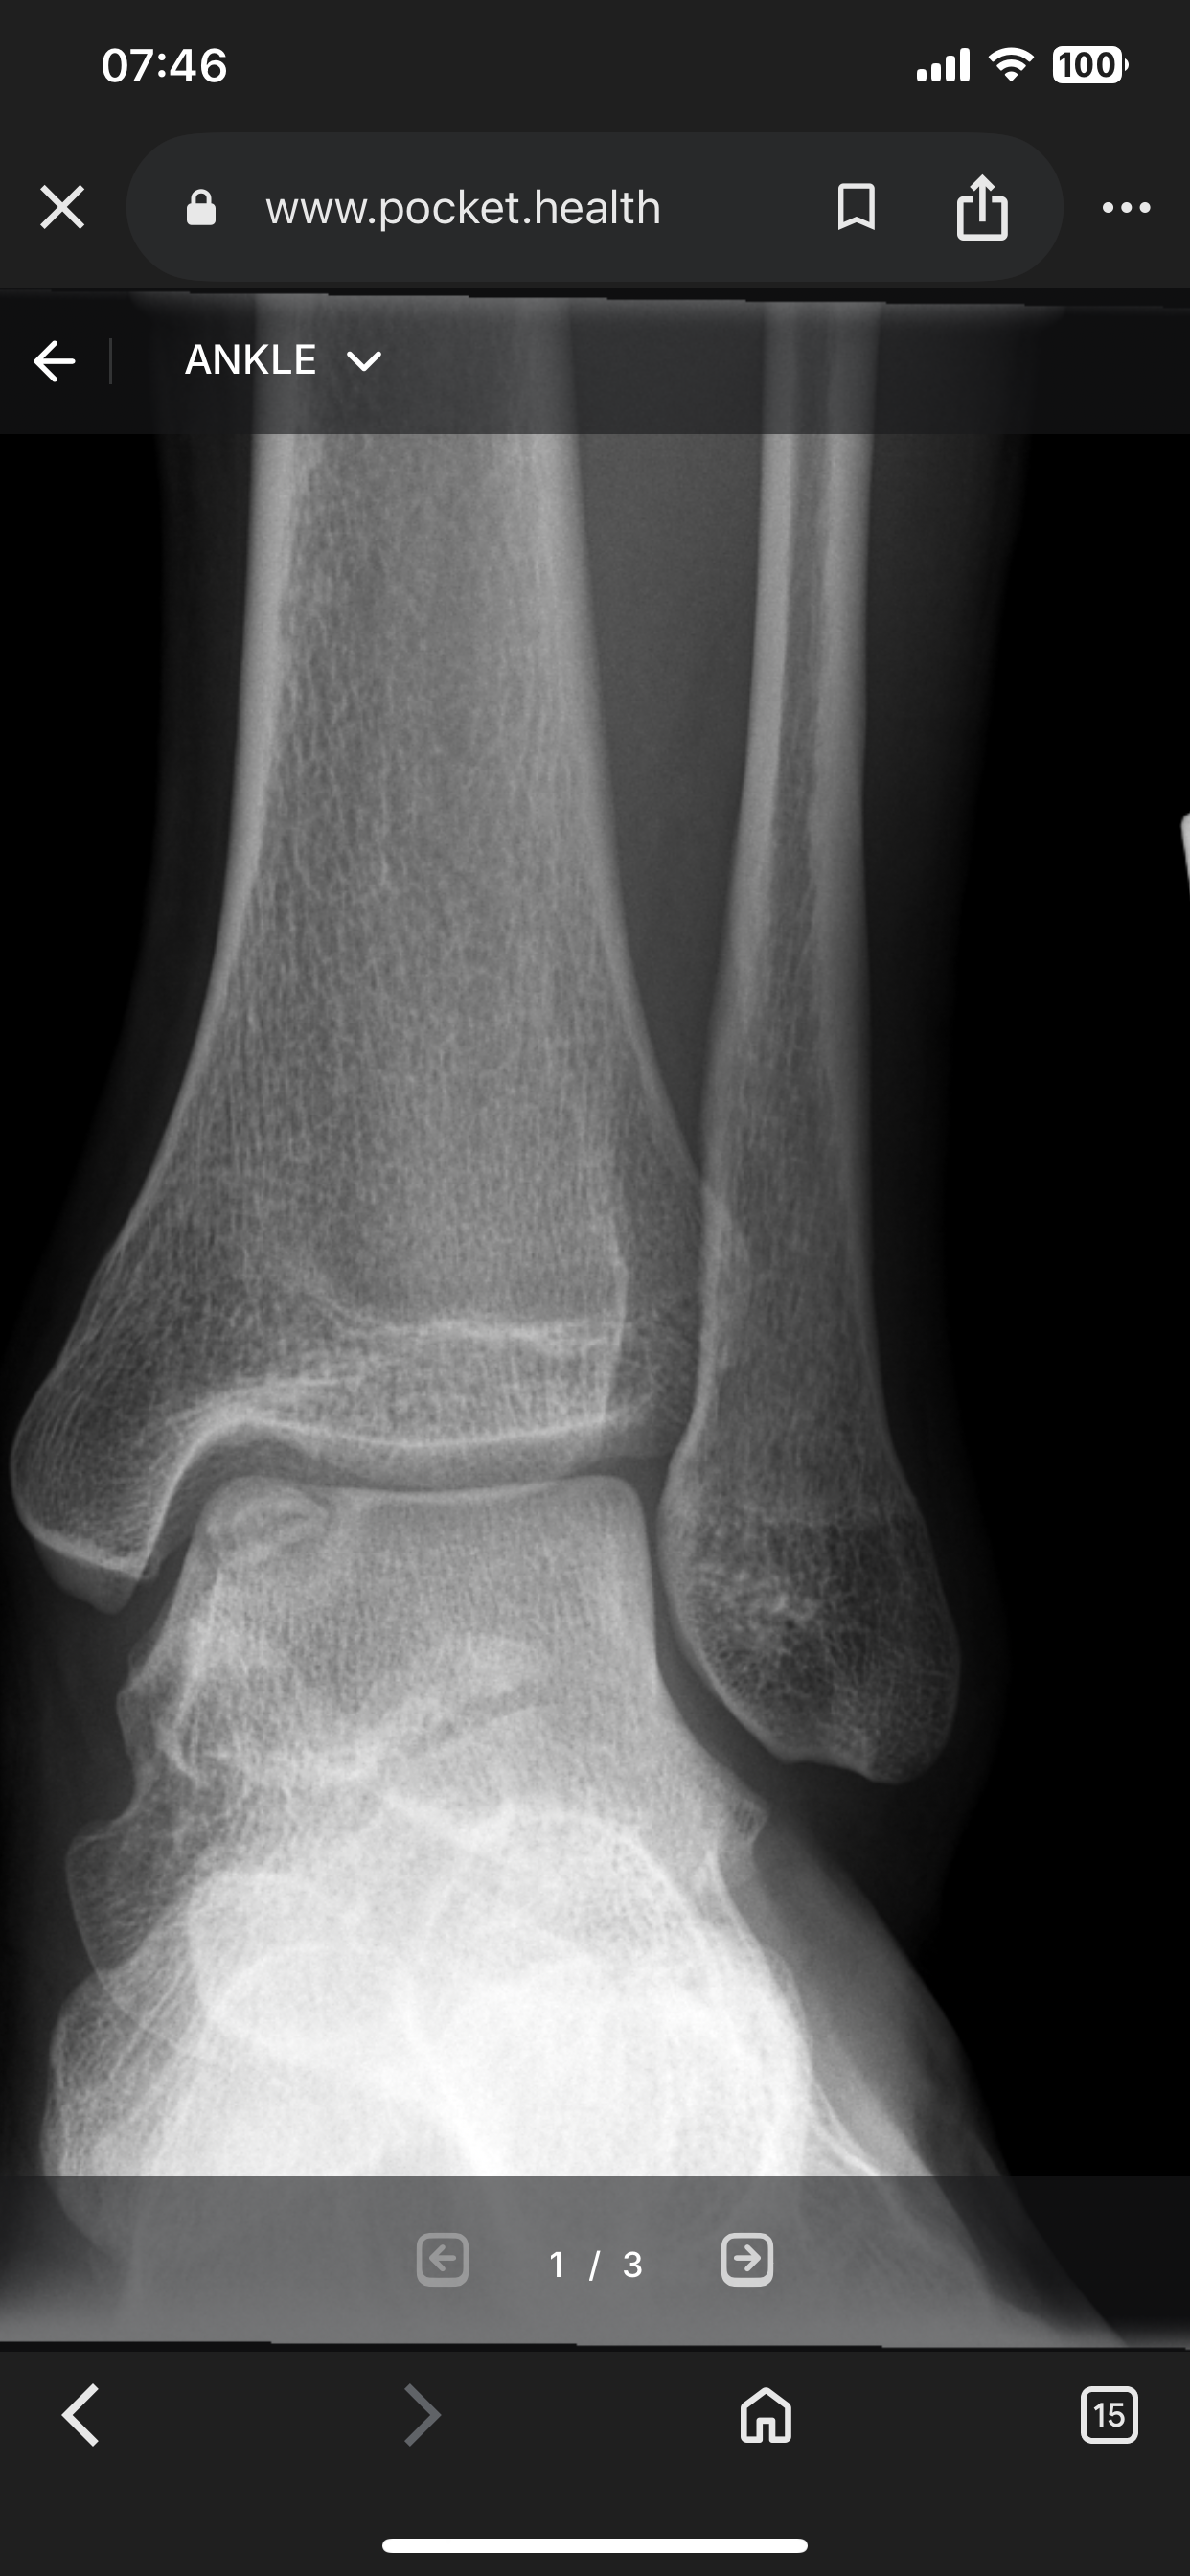

I’m fucking 5”7 and they’re fused fuck my life bro

IMG 4316